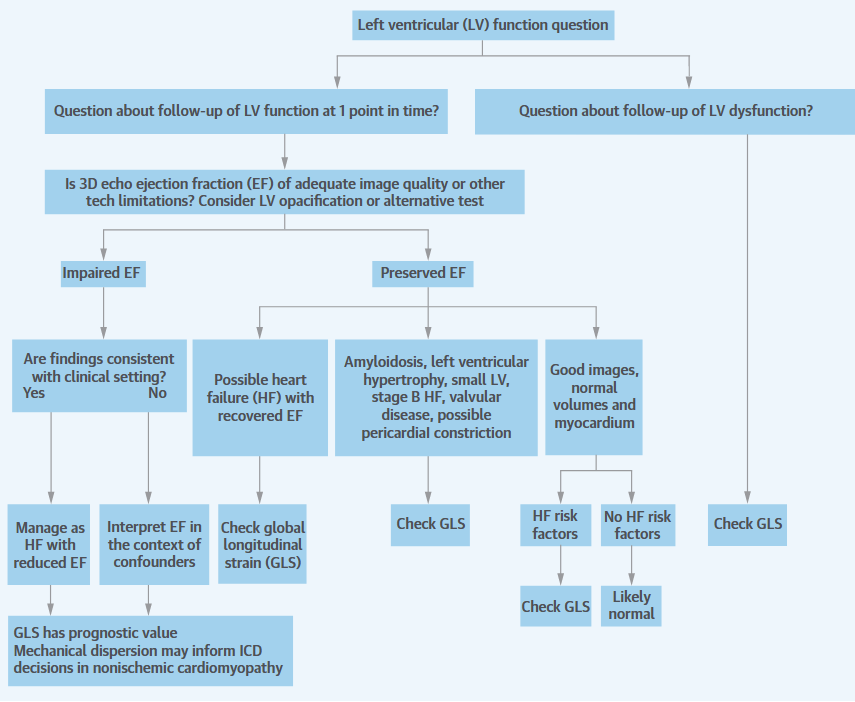

Ejection Fraction

The ejection fraction, especially the left ventricular ejection faction (LVEF), is simplest and the most well-accepted expression of global LV systolic function. EF is defined as the ratio between stroke volume and end-diastolic volume , essentially being a measurement of endocardial strain. EF is more useful marker than the stroke volume, since it accounts for the Frank-Starling relationship, which states that the stroke volume increases in response to an increase in end-diastolic volume (Kirkpatrick et al., 1976). Particularly, the excellent contrast resolution of cardiac magnetic resonance (CMR) has made itself the reference standard among non-invasive modalities.

LVEF, serving as a marker of gross LV dysfunction has become the primary criterion used in clinical practices:

Patients with heart failure (HF) can be classified into several groups: those with reduced ejection fraction (HFrEF), those with preserved ejection fraction (HFpEF), an intermediate group called HF with mid-range EF (HFmrEF). The HFrEF is defined as LVEF < 40%, while the HFpEF is defined as LVEF >= 40% or 50%. However, it doesn't mean patients with HFpEF have normal systolic function (Marwick, 2018). An additional group hF-Recovered (HFrecEF) may be defined as patients who have documented history of EF < 50% (Basuray et al., 2014). EF has been shown to have prognostic, as higher LVEFs are associated with a linear decrease in mortality, particularly with EF < 40%. However, increases above 45% are not associated with further reductions in mortality (Solomon et al., 2005).

It now occupies a central position in guidelines for the use of implantable cardioverter-defibrillator device (ICD) when recommended for primary prevention of LV sudden cardiac death.

up to an LVEF of 45% among heart failure patients. However,

Additionally, it is an important parameter to monitor LV function in the course of cardiotoxic chemotherapy (chemotherapy drugs that can cause damage to the heart). If during chemotherapy, LVEF decreases > 10% from baseline to a final LVEF below 53%, patients must be referred to the cardio-oncology unit to consider heart failure therapy.

Moreover, in patients with valvular diseases, LVEF is also used as one of the criteria to determine management. Aortic valve replacement is recommended for asymptomatic patients with severe aortic stenosis (AS) or chronic severe aortic regurgitation (AR) and LVEF < 50%. Mitral valve surgery is considered for asymptomatic patients with LVEF <= 60% (Kosaraju et al., 2024).

An ejection fraction of <35% is important in decision-making regarding device therapy, either with implantable defibrillators or cardiac resynchronisation therapy. (ACC/AHA/NASPE 2002 Guideline Update for Implantation of Cardiac Pacemakers and Antiarrhythmia Devices, n.d.)

However, LVEF still has a number of important limitations and may provide suboptimal evaluation. Firstly, the ejection fraction is load-dependent, meaning that it cannot be interpreted as a reflection of contractility in the absence of knowledge about afterload and preload. Instead, the performance of a pressure-volume loop may better facilitate the understanding of contractility (Marwick, 2013). In addition, the ejection fraction is influenced by heart rate. The increased stroke volume associated with bradycardia may lead to overestimation of the true ejection fraction, and conversely in tachycardia, the reduced stroke volume may lead to underestimation of the actual function (Marwick, 2013).

EF has a number of important limitations

EF AND VOLUMES. In general, left ventricular ejection fraction (LVEF) is more useful than stroke volume as a marker of LV function, because it takes into account the Frank-Starling relationship.

LVEF is mainly affected by preload, afterload, and contractility,

WHAT EF HIDES. A major limitation of EF is that it is sometimes a source of disproportionate focus, to the exclusion of other features.